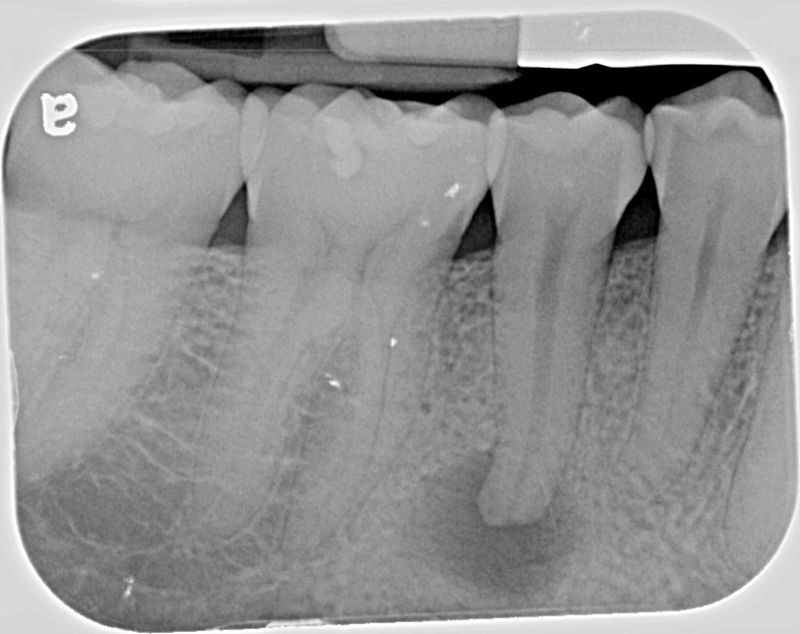

from www.quia.com

Interpreting the information from a radiograph is notoriously subjective; Discuss reasons for limiting the number of exposures. Basic tips for root canal xrays. Diagnostic radiographs allow identifying periapical lesions. Radiographs are the most accurate and least subjective diagnostic aids available. Discuss special applications of radiography to endodontics. Endodontics aims to prevent or eliminate apical periodontitis. Radiographs aid in making an endodontic diagnosis; Identify normal anatomic features in the maxilla and mandible on radiographs. Describe the importance of radiographs in endodontic diagnosis, treatment, and postoperative evaluation.

Quia Endo Xrays